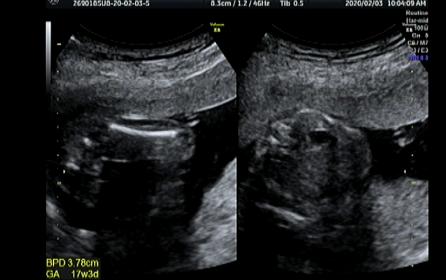

17weeks 5days ultrasound, please guess

I am new here and I am Japanese. In Japan, the doctor usually doesn't tell the gender before 22 weeks. But I already have 3 boys and 1 girl and they really would love to have one more girl so I am so nervous and would like to know the gender as soon as possible. at the 12 weeks and 0day, I thought I saw a boish nub, so I have been in a depression since. I am not sad because of the gender result but I am too afraid of what the other people will say to me if it's a boy. but when I saw the ultrasound at 17 weeks and 5 days, I saw a lips or a leave instead of penis. Is it a girl? I would like you ladies to guess the gender, please. Thanks.

Attachment 42374Attachment 42375